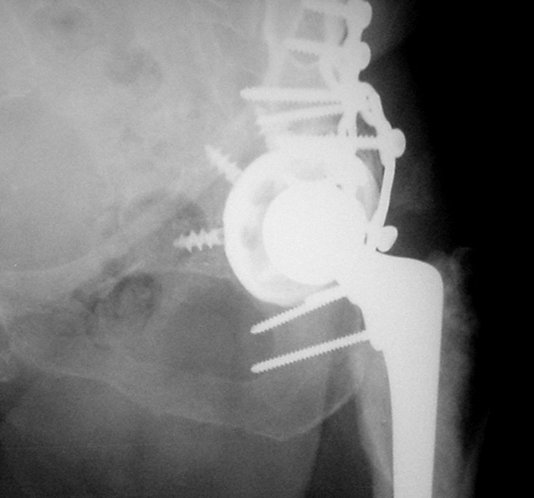

Обратились коллеги из городской больницы N36. Женщине 39 лет по поводу диспластического коксартроза около года назад выполнено эндопротезирование правого тазобедренного сустава. Вчера ехала на госпитализацию на протезирование второго сустава, и попала в аварию.

Получила поперечный перелом правой вертлужной впадины (снимок прилагается) с переломом ветвей лонной кости на другой стороне (inletview также в приложении), а также поперечный перелом дистального метафиза бедра на этой же стороне. Что посоветуете в отношении протеза и впадины? Спасибо заранее.

A colleague of mine from another hospital requests opinion. A female 39 years old was operated ~1 year ago - right side THA for hypoplastic hip. Yesterday she was going to the hospital for THA ofthe second hip but got involved in a car accident.She admitted with right acetabular and left rami fractures (images attached). Also trasverse fracture of the right distal femur.Seeking your advice regarding the acetabular fracture. THX!

Ножка Алтимед, а чашка цементая???? Хороший гибрид. Насколько позволяет рентгенограмма, можно судить, что чашка стабильна (за счет цемента и арматуры в виде винтов). Нужен постельный режим не менее 6 недель.

Ситуация редкая и нестандартная. Складывается впечатление, что эндопротез вертлужной впадины стабилен. Я бы выполнил остеосинтез перелома в/впадины реконструктивной пластиной. Эти переломы срастаются хорошо.

Установлена RM-чашка бесцементная,ножка тип Цвайммюллер производства Мathys,сделана костная пластика.В настоящее время необходим остеосинтез реконструктивной пластиной без удаления чашки,так как чашка стабильна.